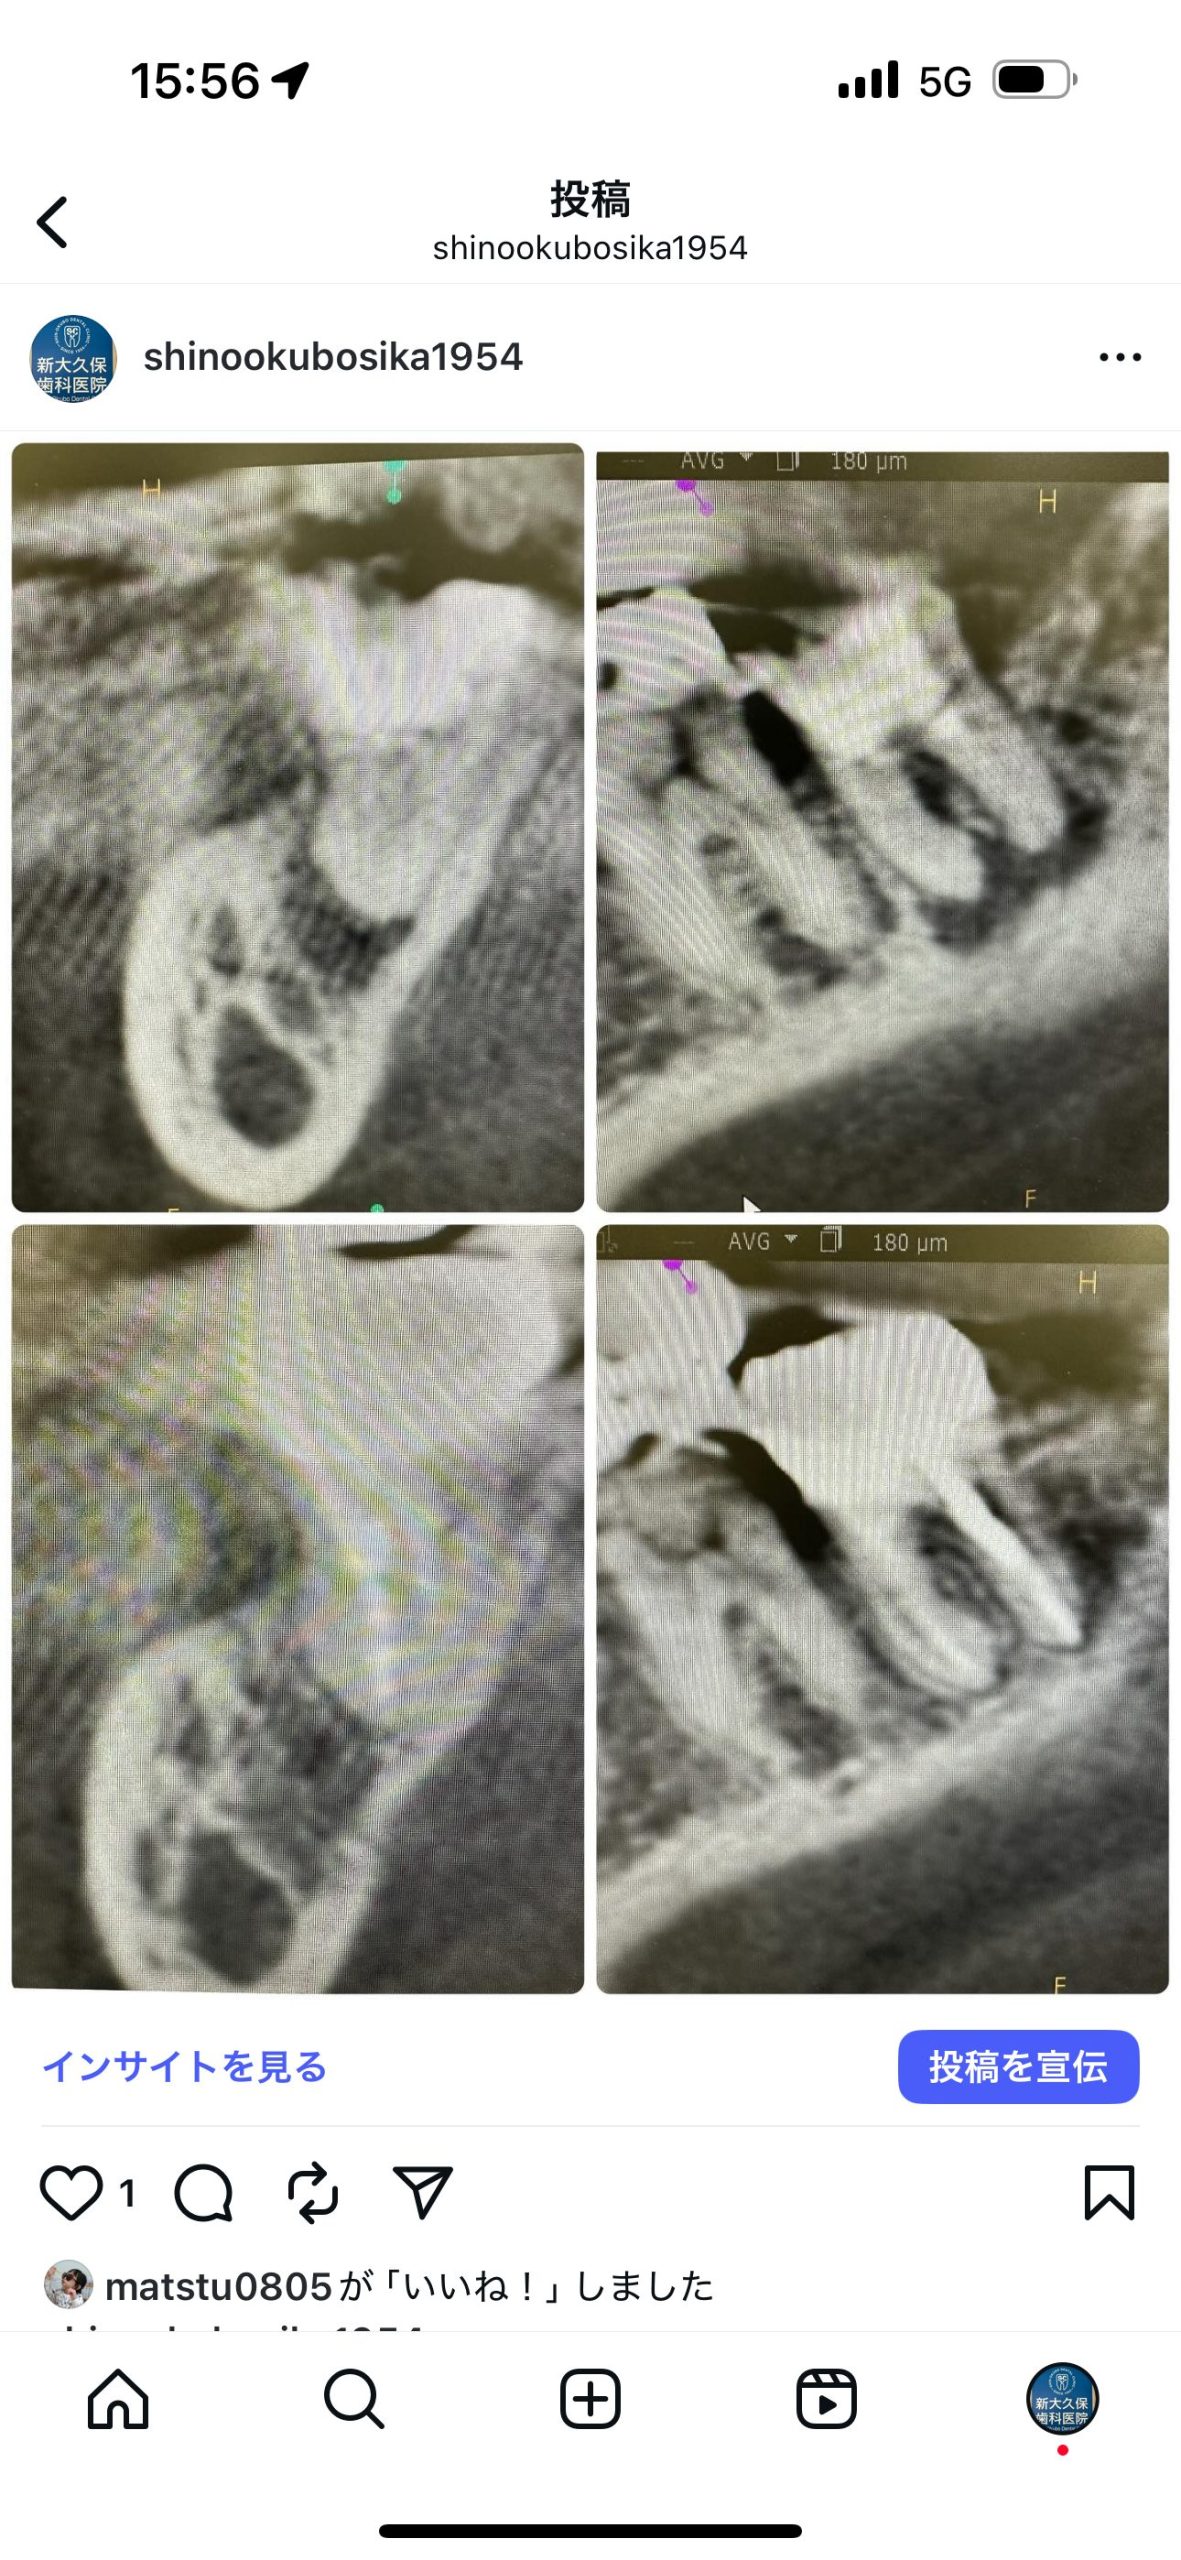

根管治療の定期検査

根充後8ヶ月経過、CT撮影

非常に良く治っている💪

秘密兵器ヤグレーザーが助けてくれていますね

あとMTAセメント様々です🙏